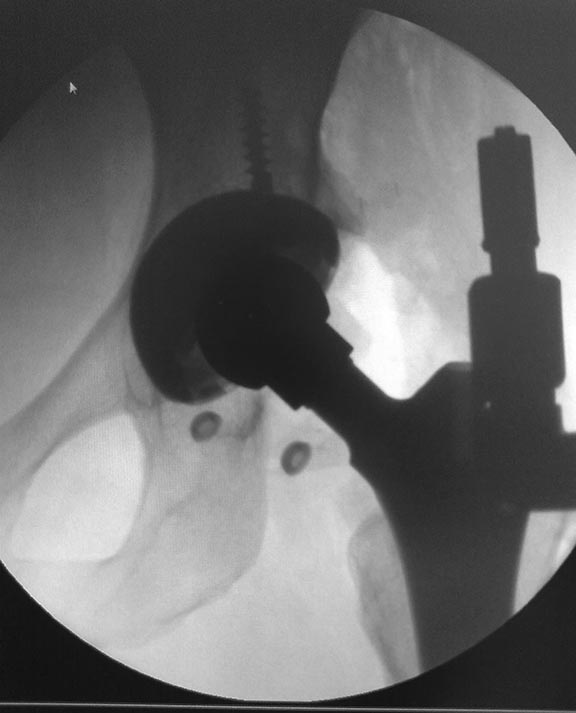

Все получилось из переднего доступа по Лайт-Кегги под эопом конечно смотрели казалось нестабильна,но на самом деле чашка не качалась,остеоинтеграция была только в зоне винтов , остальное рубцова ткань -гладкая и блестящая.После сбивания головки бедро в положении внутренней ротаци сместили вверх и впадина очень хорошо доступна. Установили чашку DePuy Pinnacle с антеверсией 20 гр. Востановить офсет удалось с головкой DePuy +12. Рентген контроль на С-дуге интраоперационно.